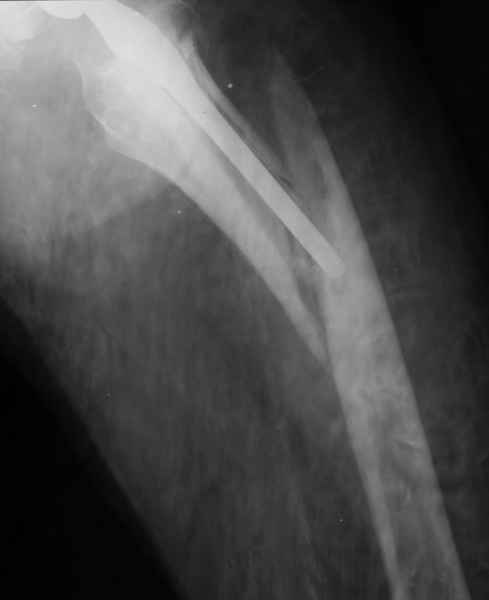

Хочется показать два подобных случая, П-ка З. 72 лет и п-т Г. 80 лет. Сразу принимаю замечание, что это были ножки цементной фиксации, просто под руками не было бесцементника.